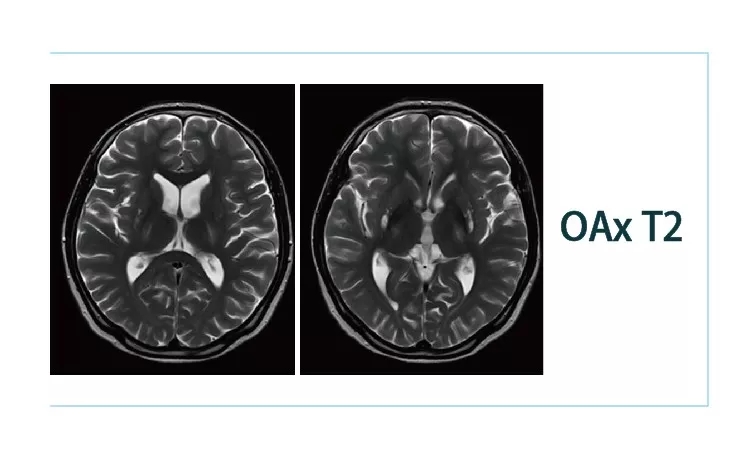

【朗润影像档案】20190216磁共振影像病例结果讨论

【朗润影像档案】20190125磁共振影像病例结果讨论

【朗润影像档案】20190118磁共振影像病例结果讨论

【朗润影像档案】20190111磁共振影像病例结果讨论

【朗润影像档案】20190104磁共振影像病例结果讨论

【朗润影像档案】20181229磁共振影像病例结果讨论

【朗润影像档案】20181221磁共振影像病例结果讨论

【朗润影像档案】20181214磁共振影像病例结果讨论

【朗润影像档案】20181207磁共振影像病例结果讨论

【朗润影像档案】20181130磁共振影像病例结果讨论

【朗润影像档案】20181123磁共振影像病例结果讨论

【朗润影像档案】20181116磁共振影像病例结果讨论